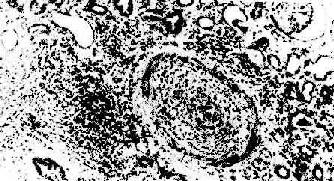

(1)细胞型排斥反应:常发生在移植后几个月,临床上表现为骤然发生的移植肾功能衰竭。镜下可见肾间质明显水肿伴有大量细胞浸润,以单核细胞和淋巴细胞为主,并夹杂一些具有嗜酸性胞浆和水泡状胞核的转化淋巴细胞和浆细胞。免疫组化染色证实有大量CD4+、CD8+细胞存在。肾小球及肾小管周围毛细血管中有大量单核细胞,间质中浸润的淋巴细胞可侵袭肾小管壁,引起局部肾小管坏死(图4-4)。

肾移植急性排斥反应

图4-4 肾移植急性排斥反应

肾间质水肿,肾小管上皮细胞变性,间质及毛细血管内有大量单核细胞